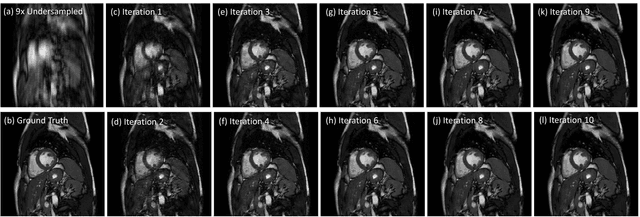

Abstract:Inspired by recent advances in deep learning, we propose a framework for reconstructing dynamic sequences of 2D cardiac magnetic resonance (MR) images from undersampled data using a deep cascade of convolutional neural networks (CNNs) to accelerate the data acquisition process. In particular, we address the case where data is acquired using aggressive Cartesian undersampling. Firstly, we show that when each 2D image frame is reconstructed independently, the proposed method outperforms state-of-the-art 2D compressed sensing approaches such as dictionary learning-based MR image reconstruction, in terms of reconstruction error and reconstruction speed. Secondly, when reconstructing the frames of the sequences jointly, we demonstrate that CNNs can learn spatio-temporal correlations efficiently by combining convolution and data sharing approaches. We show that the proposed method consistently outperforms state-of-the-art methods and is capable of preserving anatomical structure more faithfully up to 11-fold undersampling. Moreover, reconstruction is very fast: each complete dynamic sequence can be reconstructed in less than 10s and, for the 2D case, each image frame can be reconstructed in 23ms, enabling real-time applications.